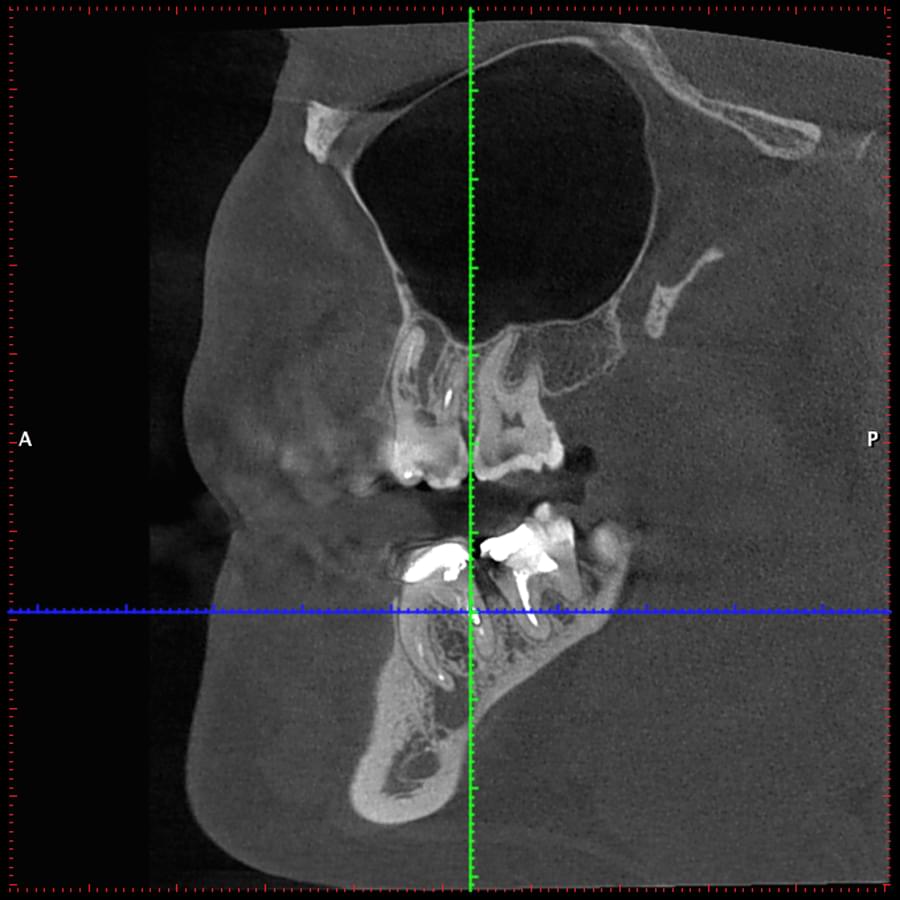

3D цефалометричний аналіз є сучасною технологією, яка дозволяє отримувати точніші,

комплексніші та надійніші дані про зубну та скелетну структуру. Ця технологія може стати

великим кроком в перед для ортодонтів, які хочуть забезпечити найкраще можливе лікування

своїх пацієнтів.

Основні переваги 3D цефалометричного аналізу:

Точність: 3D цефалометричний аналіз забезпечує точніше визначення розмірів та відстаней між

зубами та кістковими структурами.

Комплексність: ця технологія дозволяє отримувати детальні дані про різні структури, такі як

кістка та м'язи, що дозволяє ортодонтам докладніше досліджувати деякі патології та планувати

лікування.